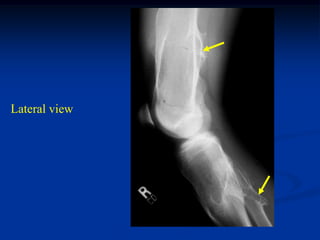

Case #556

55 year male with

enchondroma tibia

Lateral view